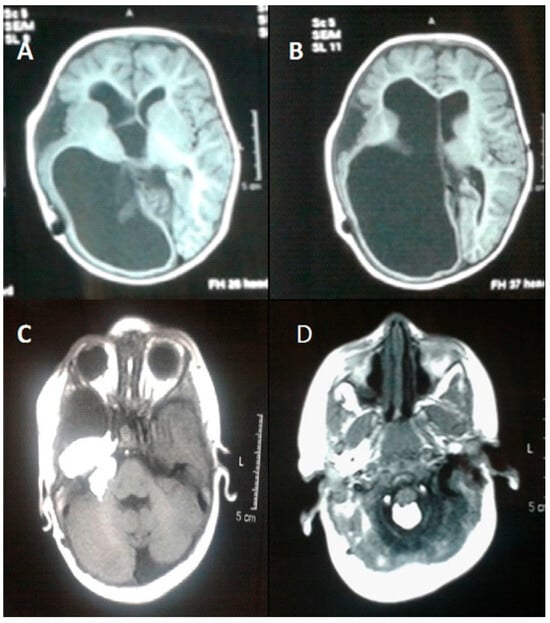

Melanoma is a highly aggressive skin cancer primarily linked to ultraviolet (UV) radiation. However, the potential role of ionizing radiation from radiotherapy in melanoma development remains unclear. This review synthesizes data from epidemiologic s...